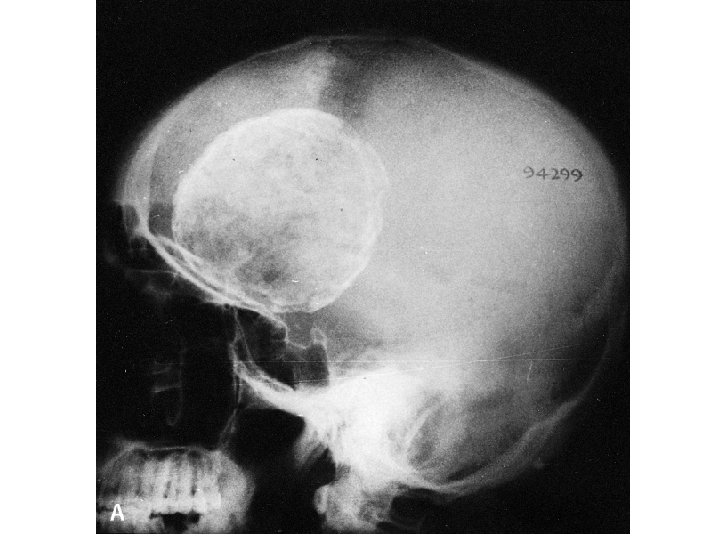

Pathology • E. granulsus cysts are large, spherical, and well demarcated from surrounding tissue. • within the CNS, these cysts may be located in the brain parenchyma, ventricular system, subarachnoid space, epidural space, orbits, and both the epidural and subarachnoid spaces in the spinal canal.

Pathology • epidural cysts tend to be associated with vertebral bone erosion. • Primary hydatid disease of the heart may be the source of an embolic cerebral infarction, usually in the territory of the middle cerebral artely.

CYSTIC HYDATID DISEASE OF THE BRAIN • Dowling's technique: hydrostatic expulsion of the entire cyst by irrigation of saline solution between the lesion and the surrounding nervous tissue. • The aim of this technique is to remove the cyst without damaging its walls.